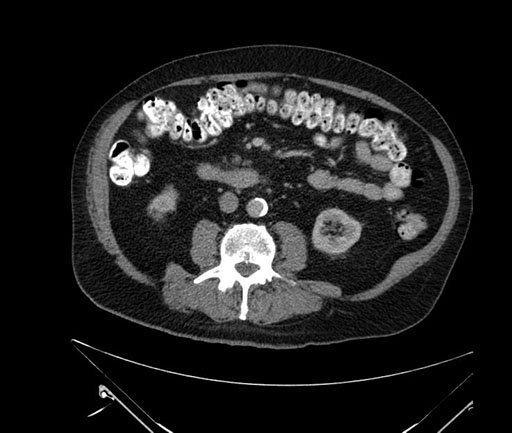

Whipple (pancreaticoduodenectomy) [case 7]

Imaging Analysis

Look through the patient's CT scan to identify any areas of concern for the necessary procedure.

Axial - stented